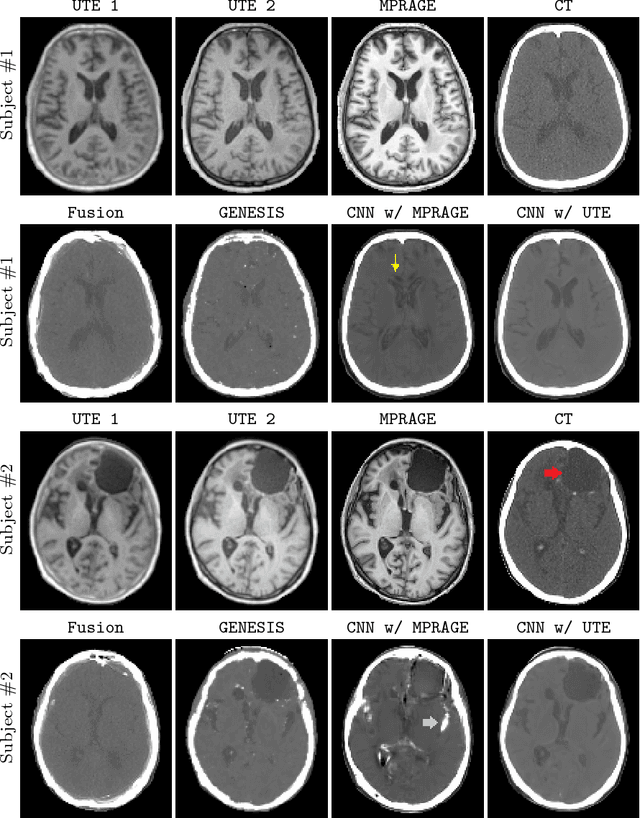

With the increasing popularity of PET-MR scanners in clinical applications, synthesis of CT images from MR has been an important research topic. Accurate PET image reconstruction requires attenuation correction, which is based on the electron density of tissues and can be obtained from CT images. While CT measures electron density information for x-ray photons, MR images convey information about the magnetic properties of tissues. Therefore, with the advent of PET-MR systems, the attenuation coefficients need to be indirectly estimated from MR images. In this paper, we propose a fully convolutional neural network (CNN) based method to synthesize head CT from ultra-short echo-time (UTE) dual-echo MR images. Unlike traditional $T_1$-w images which do not have any bone signal, UTE images show some signal for bone, which makes it a good candidate for MR to CT synthesis. A notable advantage of our approach is that accurate results were achieved with a small training data set. Using an atlas of a single CT and dual-echo UTE pair, we train a deep neural network model to learn the transform of MR intensities to CT using patches. We compared our CNN based model with a state-of-the-art registration based as well as a Bayesian model based CT synthesis method, and showed that the proposed CNN model outperforms both of them. We also compared the proposed model when only $T_1$-w images are available instead of UTE, and show that UTE images produce better synthesis than using just $T_1$-w images.